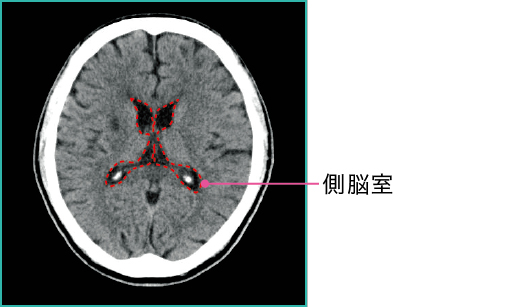

1)CTでの水頭症の鑑別

CTでは髄液は低吸収域で(=黒く)描写されます。正常な頭部CTでは図1-1のように描写されますが、それに対して、水頭症のある場合には図1-2のように脳室が拡大している画像が得られます。

●赤い点線は側脳室を示している

●側脳室が通常より拡大している